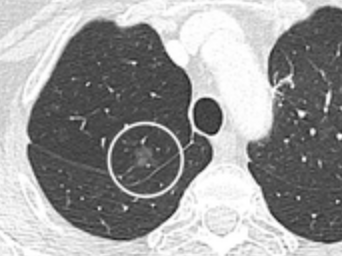

CT — Lung Nodule with Vascular Convergence

CT showing lung nodule with converging pulmonary vessels, a sign suggesting malignancy

CT Downloaded 2026-03-15

Ct

Lung Window 120 kVp W:1500 L:-600

Wikimedia Commons: CT of lung nodule with vascular convergence.png